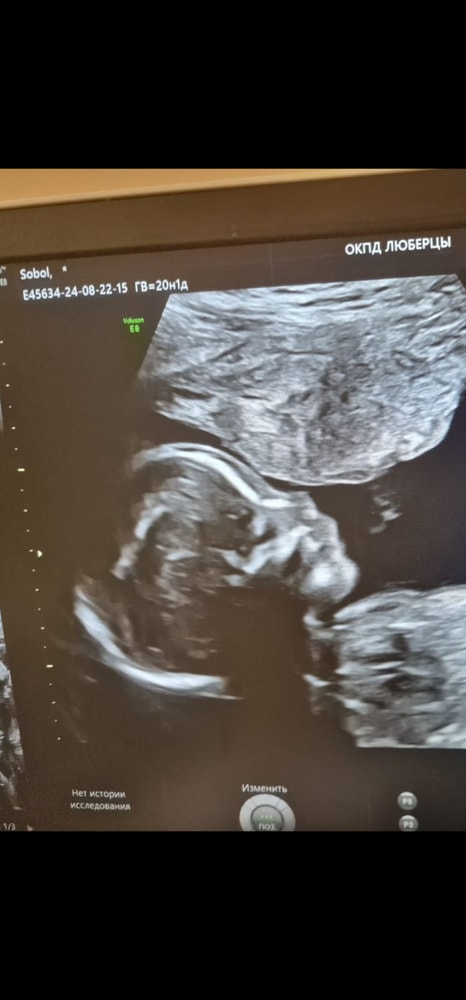

У моего на УЗИ тоже был такой носик, собственно, и родился с таким, очаровательный нос, очень красивый. Я сказала - слава богу, что не как у меня🙈

У меня на таком узи- фото был похож на Караченцева, родился- не похож.

Если вы мечтали о римском ли греческом профиле у ребенка, то к сожалению, такому не бывать)) Он будет похож на вас или вашу родню.

Обычно такие детские головушки бывают на вышивках. Какая милота!

Нормальный, он может и не курносый вообще. Дочка родилась с приподнятым носом-пуговкой, сейчас 2 года и совершенно другой